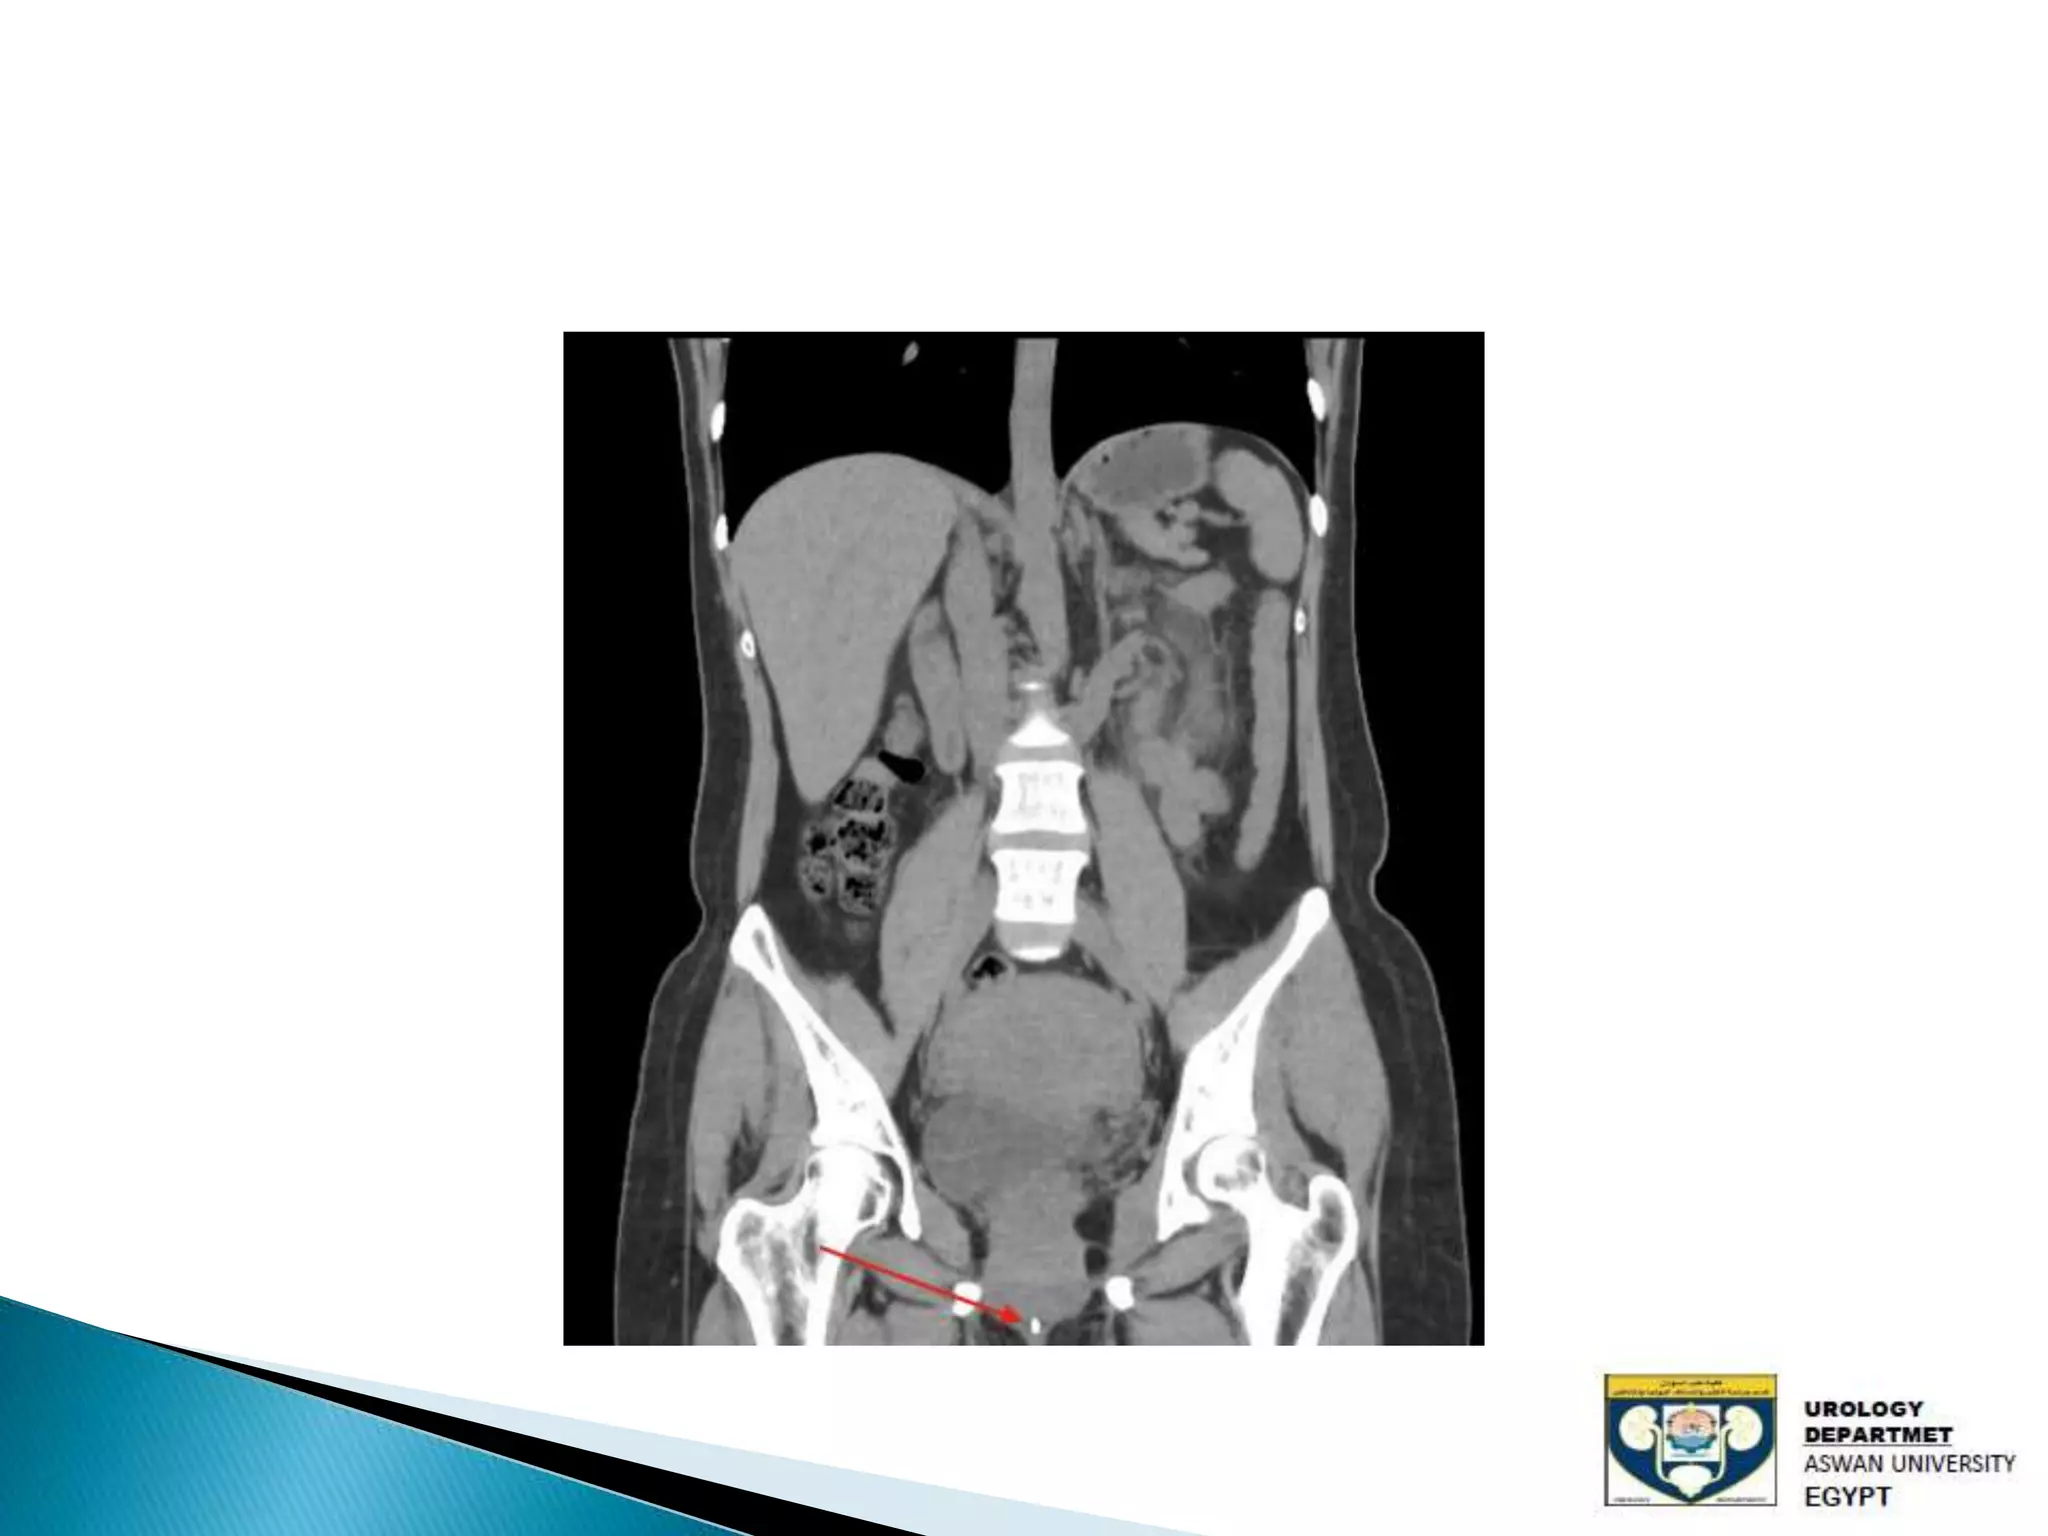

The document discusses urinary tract stones, detailing their types, causes, symptoms, and diagnostic methods. It highlights the risk factors such as infections and obstructions, with men being more commonly affected. Treatment options include various surgical methods, particularly for managing bladder outflow obstruction and lithiasis.